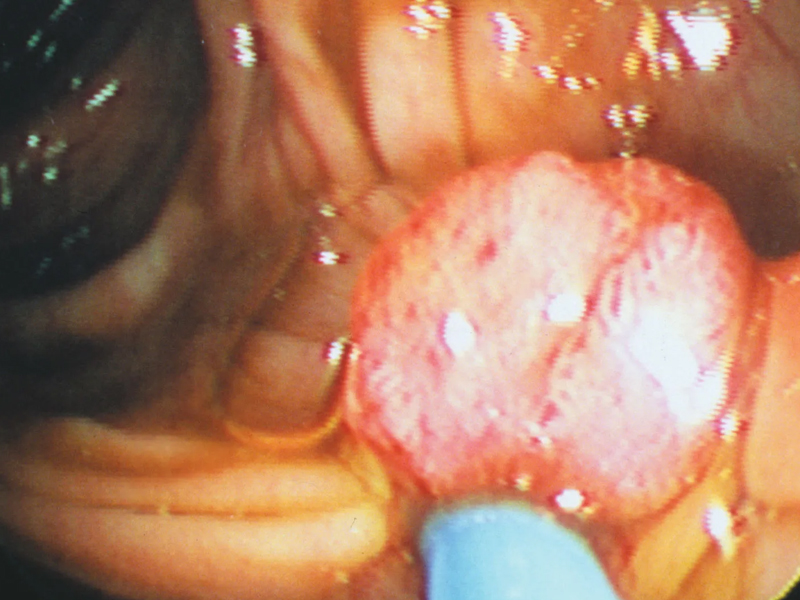

2. 心慌、伴隨悶痛

感覺胸部有悶痛的感覺或是有壓迫感、心慌、身體乏力、頭暈等不適,請立即送醫!再拖就晚了。